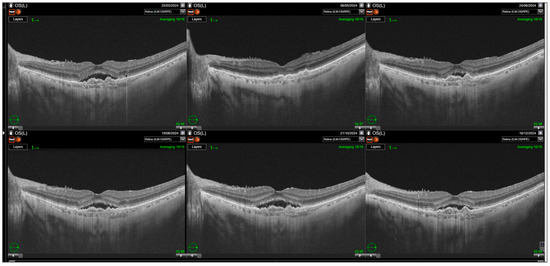

Purpose: To evaluate anatomical and functional outcomes after switching from aflibercept to faricimab in patients with neovascular age-related macular degeneration (nAMD) with suboptimal response. Methods: This retrospective study included 72 eyes of 66 patients with nAMD previously treated with intravitreal aflibercept using a treat-and-extend regimen. Indications for switching included persistent retinal fluid, pigment epithelial detachment (PED), lack of best-corrected visual acuity (BCVA) improvement, or inability to extend treatment intervals beyond four weeks. Patients received three monthly loading doses of faricimab followed by individualized 8- to 16-week dosing. Follow-up comprised six visits over a mean of 8.5 ± 1.4 months. Outcomes included BCVA (logMAR), retinal morphology (subretinal fluid—SRF; intraretinal fluid—IRF; pigment epithelial detachment—PED), central subfoveal thickness (CST), and treatment interval changes. Results: Switching to faricimab led to significant short-term anatomical improvement, primarily reduction in subretinal fluid (p < 0.0001), with maximal effect during the loading phase. Resolution of SRF was significant at the end of the follow up; however, IRF changes were transient and not sustained beyond three months. PED reduction reached borderline significance (p = 0.0455). CST decreased during the loading phase (p < 0.0001) but returned to baseline thereafter. BCVA improved only after loading (p = 0.0287) but not at final follow-up. Treatment intervals were extended by a mean of ~2 weeks (p < 0.0001), increasing in 80% of eyes. Eyes with fewer prior injections and better baseline BCVA achieved superior final visual outcomes. Conclusions: Switching to faricimab provides short-term anatomical benefits and treatment-interval extension without sustained visual gain. Functional improvements tended to be greater in patients with fewer injections and shorter treatment duration prior to switch. Full article

Show Figures

Figure 1